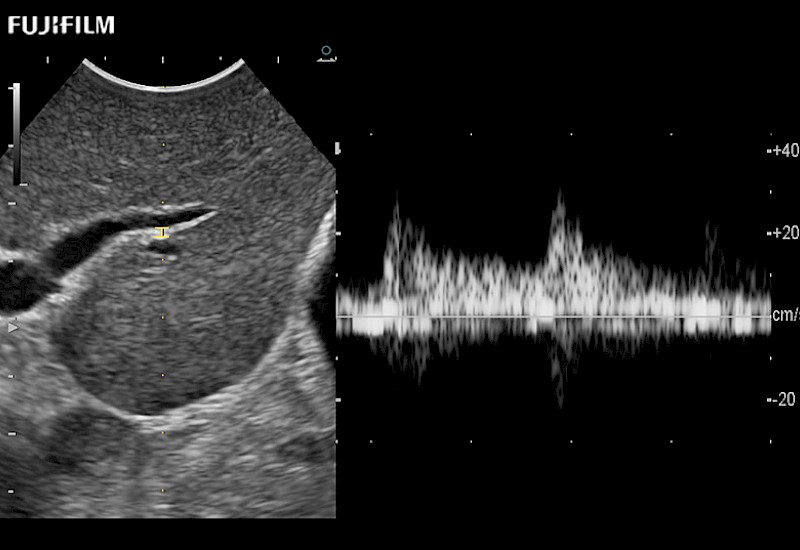

The ARIETTA 750 incorporates all of the proven technologies and functions that medical professionals have come to expect from Fujifilm Healthcare.

ARIETTA 750 is the definitive diagnostic ultrasound solution for any clinical setting - Private Office, Imaging Center, or Hospital. The ARIETTA platform provides the ultimate in clinical performance with its state-of-the-art features and large user-friendly display.

The ARIETTA 650 DI combines trusted Fujifilm Healthcare technologies and features tailored for surgical oncology.

Designed to meet the demands of surgeons, the ARIETTA 650 DI offers precise guidance. Its advanced capabilities and large, intuitive display offer accurate and efficient care in operating rooms and specialized surgical settings.